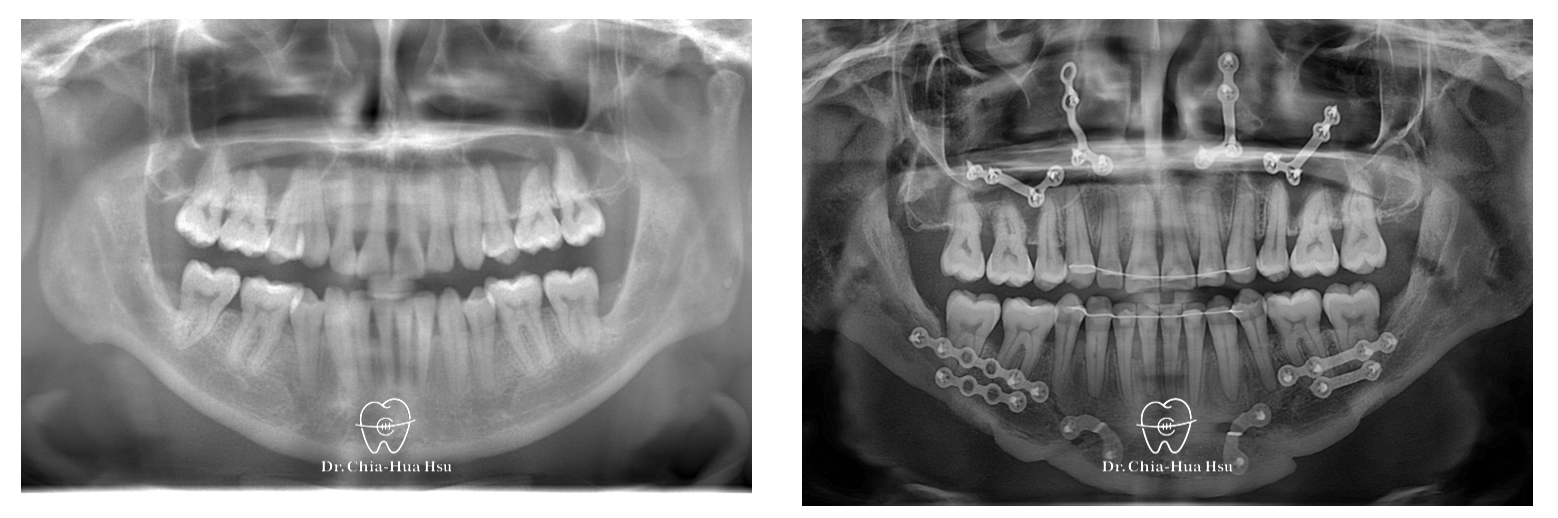

治療前

治療後

• 治療方式:使用傳統金屬矯正器,合併正顎手術(雙顎),以手術方式將下顎骨前移改善呼吸道與外觀。

治療過程:患者有下顎後縮合併有睡眠呼吸中止症,接受了雙顎前移手術。